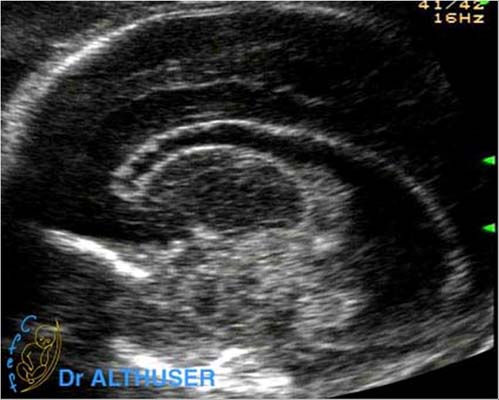

Selon la date de contamination, les lésions sont dues soit à une interférence dans l'organogenèse en cas d'infection précoce, soit à l'infection d'organes déjà formés. Les lésions cérébrales dépendent de la date de contamination du fœtus et, éventuellement, des réactivations successives. Le virus peut provoquer d'une part des lésions de nécrose focale par destruction cellulaire, suivie de lésions inflammatoires secondaires sous forme de granulomes à CMV, puis de sclérose. Pendant les quatre premières semaines surviennent des lésions de cytolyse, de vascularite et de ventriculite. Elles sont responsables de la constitution, au cours des semaines suivantes, de zones de nécrose et de sclérose, de thromboses et de nodules microgliaux. Il en résulte une destruction plus ou moins étendue du tissu cérébral avec atrophie, porencéphalie, gliose, calcifications parenchymateuses et, éventuellement, dilatation ventriculaire ou anomalies de migration et de gyration. La coexistence fréquente de lésions d'âge différent est un argument en faveur de réinfections successives (92).

La séméiologie échographique décrite par les différents auteurs comporte les signes suivants :